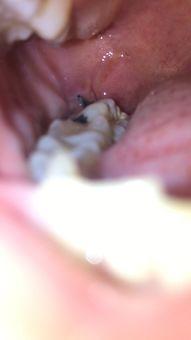

最近是不是也被那些顽固的跖疣给困扰了呢?别急,今天就...